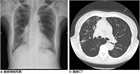

1. 痰に血液の混じったものを血痰、血液が下気道から喀出されたものを喀血としている。

1. 鼻出血、口腔内からの出血、消化管出血(吐血)ではなく、血痰か喀血かを確認する必要がある。